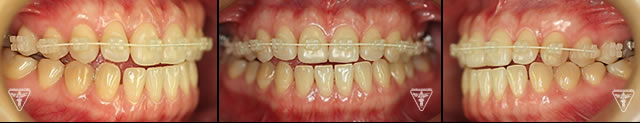

治療後

治療前後の比較